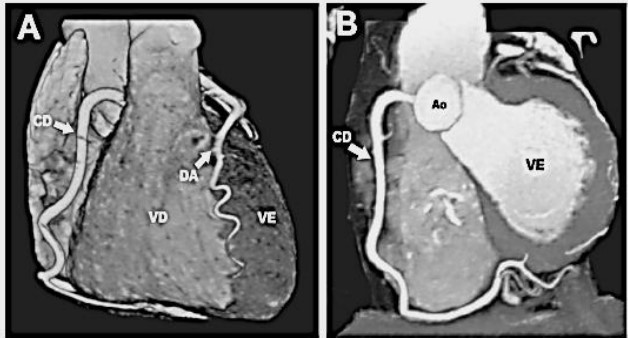

Observe as Imagens ilustrativas de um paciente que foi submetido à angiotomografia coronariana. Neste caso, a angiotomografia foi inteiramente normal, excluindo a presença de doença da artéria coronária (DAC). Pode ser visto o ventrículo direito (VD) e o ventrículo esquerdo (VE). O tipo de sangue que “chega” no VE e o vaso que conduz o sangue durante a sístole deste ventrículo em direção dos tecidos pode ser encontrado na opção: